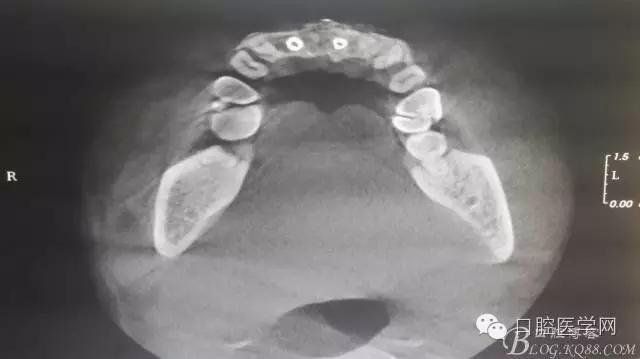

植入種植體左側(cè)3510,右側(cè)4010,植骨Bioss,蓋膜Cytoplast。骨膜減張垂直褥式縫合加間斷縫合。

之所以選擇Bioss是考慮其降解速度較慢,種植體接觸大面積為自體骨,Bioss可以很穩(wěn)定的緩慢吸收逐步引導(dǎo)骨再生。